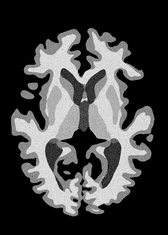

4.2 Registration to a 100 micron ex-vivo brain MRI volume

To showcase the efficacy of our method on real large scale images, we register a 250 in-vivo MRI image (Lüsebrink et al., 2017) to a 100 ex-vivo FLASH human brain volume (Edlow et al., 2019). This represents an inverse problem with more than 11.2B optimizable parameters (compared to 20M for clinical datasets), or 44.8GB of GPU memory. The entire problem does not fit on most GPUs, necessitating distributed multimodal registration. We optimize a composite transform - affine followed by a diffeomorphic mapping; details can be found in Section E.1. Multimodal deformable registration took 58 seconds on 8 NVIDIA A6000 GPUs, which is unprecedented at this resolution. Fig. 6 shows qualitative results, highlighting the ability to register highly detailed structures such as cerebellar white matter; these structures are not visible at macroscopic scales. The resultant advantages of performing registration at this scale can allow researchers to characterize the neuroanatomy at microscopic resolutions and allow morphometric analysis of cortical layers and subcortical nuclei among other structures.